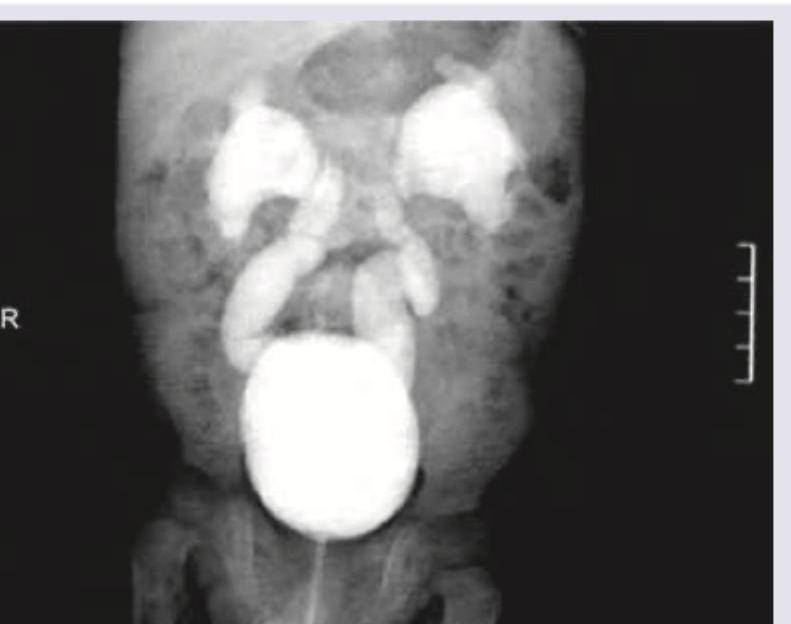

Identify the radiological investigation and finding shown in the image below:

Explanation: ***IVP showing horse shoe kidney*** - The image displays features consistent with an **Intravenous Pyelogram (IVP)**, a radiological study of the urinary tract using contrast. The large, fused renal structures at the inferior poles, forming a "U" or "horseshoe" shape, are characteristic of a **horseshoe kidney**. - In a horseshoe kidney, the **lower poles of both kidneys are fused**, typically anterior to the great vessels, which is visible here through the opacified collecting systems. *Barium enema ulcerative colitis* - A **barium enema** visualizes the colon, and typical findings in **ulcerative colitis** include loss of haustra, narrowing, and mucosal irregularities, which are not seen in this image. - The structures shown here are clearly **intravenous contrast-filled renal collecting systems**, not intestinal loops. *Hysterosalpingogram suggestive of PID* - A **hysterosalpingogram (HSG)** is an imaging test for the uterus and fallopian tubes, visualized after contrast injection. - While **pelvic inflammatory disease (PID)** can cause tubal abnormalities (e.g., hydrosalpinx), the image clearly shows structures resembling kidneys and ureters, not female reproductive organs. *Micturition cystourethrogram suggestive of VUR* - A **micturating cystourethrogram (MCUG)** assesses the bladder and urethra, primarily for **vesicoureteral reflux (VUR)**, where urine flows backward into the ureters and kidneys from the bladder. - This image shows contrast in the renal collecting systems and ureters, but it's consistent with an **IVP and an anatomical variant** (horseshoe kidney), not reflux from the bladder as would be observed during active micturition in an MCUG.